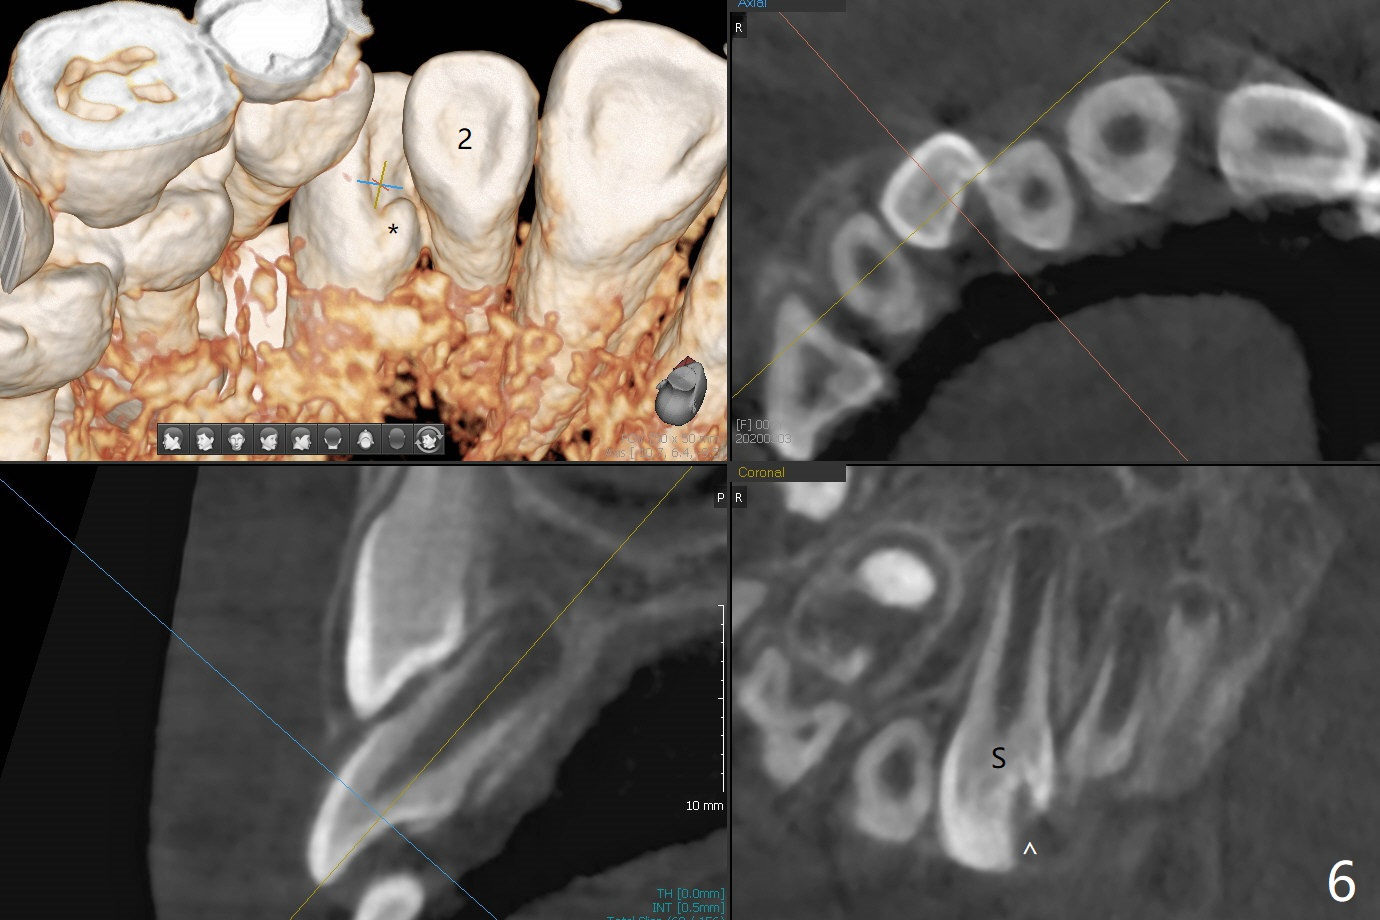

A 6-year-old woman presents to office for limited exam for caries (Fig.1). What was neglected is a super-numerary tooth (S) between UR2 and 3. One year later, the extra tooth appears to be erupting (Fig.2) and linguali-zing UR2 (Fig.3 arrow). PA shows that the extra tooth looks like a lateral (Fig.4). CT will be taken to decide which tooth needs for extrac-tion. The super-numerary tooth (S) blocks UR3 descent, as compared to that of UL3 (Fig.5). The super-numerary tooth with an abnormal cingulum (Fig.6 *) and dens in dente (Fig.6 ^) should be extracted.